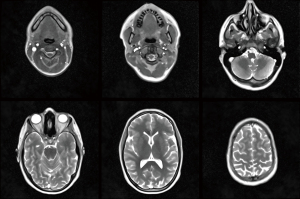

Figure 1 depicts selected transverse images of a T2/T1-weighted brain scan at 0.7 mm in-plane resolution and 3 mm slice thickness, for other parameters see Table 1. The entire sequence of serial images is recorded in cranial direction starting in the neck region. It is obtained in 43 s and shown in Video 1 running at the true acquisition and reconstruction speed (i.e., about 12 fps). Brain studies benefit from both relatively short measuring times to cope with involuntary subject movements during cross-sectional scanning and from T2/T1 contrast to provide optimal sensitivity for pathologies as demonstrated in recent pediatric neuroimaging applications (16).